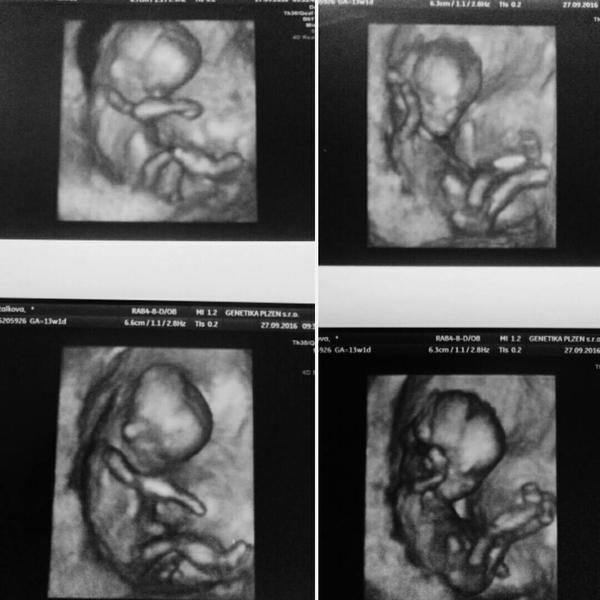

Ahoj, dnes jsem byla na UTZ vyšetření na vrozené vývojové vady v prvním trimestru, dělali mi ho na poslední chvíli (jsem 13+0) a spíš jen tak pro úplnost jsem nadhodila, jestli je na zjištění pohlaví ještě brzo, nebo ne. Pohlaví mi řekli, a teď mě spíš zajímá - vy, co vám taky pohlaví dítěte řekli takhle brzy, shodovalo se to pak se zjištěními z pozdějších UTZ a samozřejmě u porodu, nebo se spletli? Zajímá mě úspěšnost u takhle brzkých stanovení pohlaví 🙂 Díky.

Ahoj, nám řekli ve 13tt, že to vypadá na kluka, ale že radši nemáme kupovat jenom modrý oblečky 🙂 Tak jsem zvědavá, co nám řeknou v tom 20tt, to bude až v průběhu března, tak musíme taky vydržet. 🙂

U první dcery na NT screeningu asi ve 13. týdnu mi to dr taky řekla. Byla to dr, co se zabývá prenatální diagnostikou, zeptala se, jestli chci vědět pohlaví. Když jsem se ptala, jestli to už jde poznat, tak řekla, že samozřejmě, takže žádný váhání, tipování, byla si jistá. A pak už se to jen potvrzovalo.

byla jsem 13+2 u pana Vlasina v prenatalu v brne. U prvni rekl holcicka mame holcicku 🙂 a ted uz neumusel nic rikat toho pindulika jseme tam videli zretelne oba. Malej byl rozčaplej ze to snad vic neslo 😀